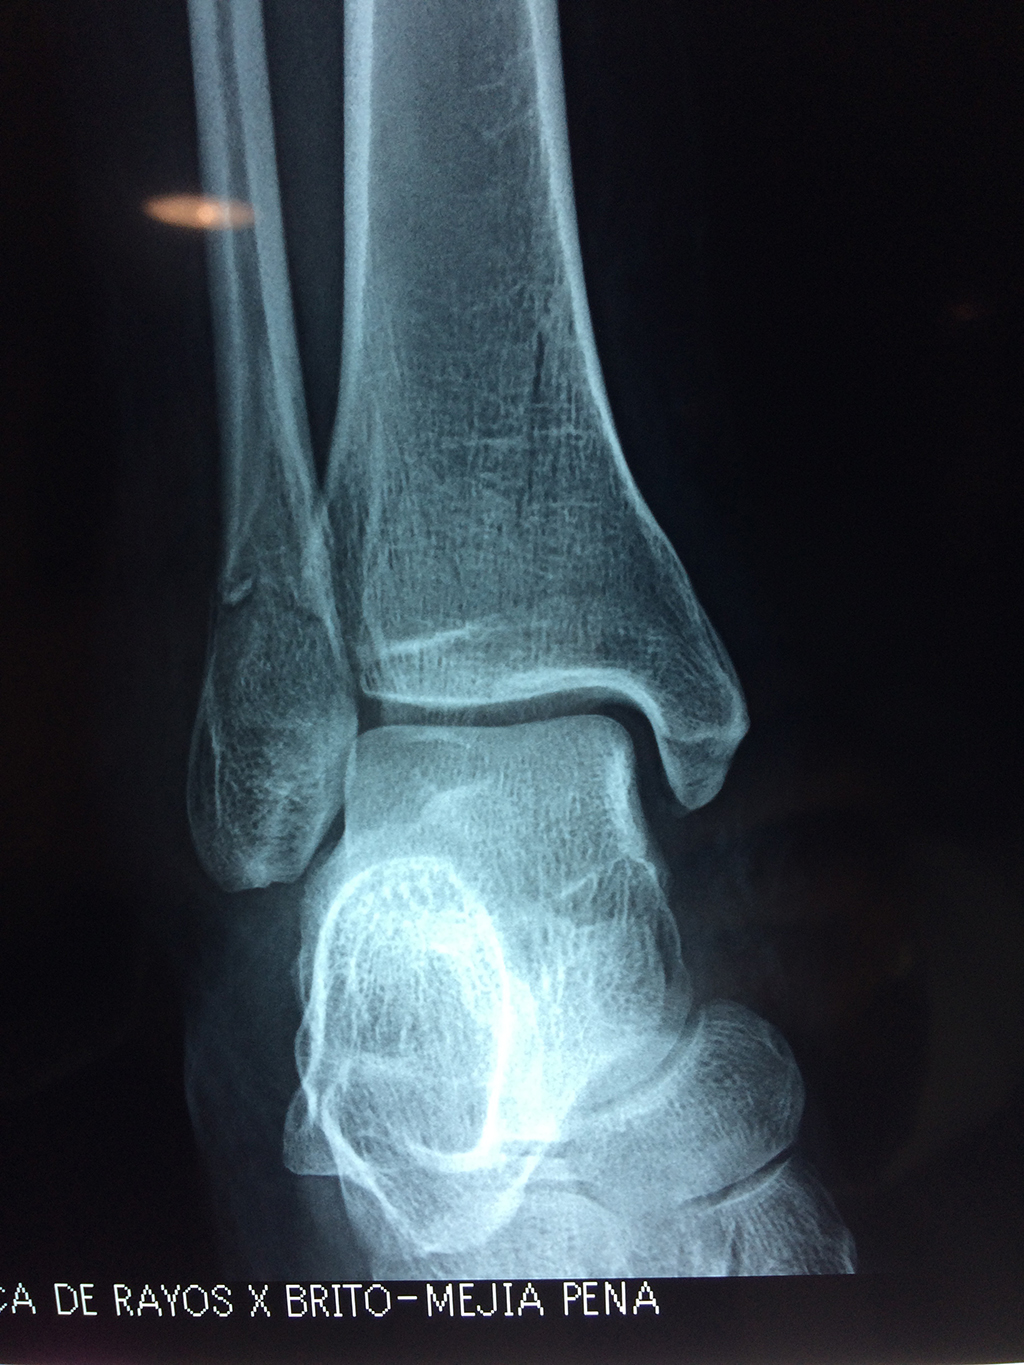

Una fractura de tobillo es la rotura de uno o más de los huesos del tobillo. Estas fracturas pueden ser:

Algunas fracturas de tobillo pueden requerir cirugía si:

- Los extremos de los huesos están desalineados entre sí (desplazados).

- La fractura se extiende hasta la articulación del tobillo (fractura intra-articular).

Cuando se necesita cirugía, es probable que esta implique el uso de clavijas de metal, tornillos o placas para sostener los huesos en su lugar mientras la fractura se consolida. Los elementos de soporte pueden ser temporales o permanentes.